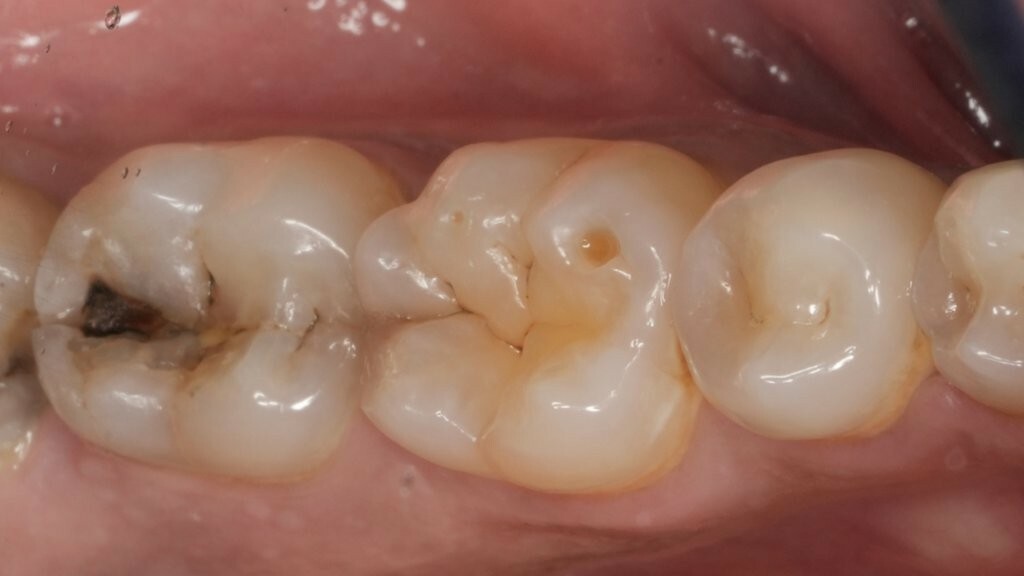

Abbildung 1: Ausgangssituation. Initiale klinische Präsentation einer ausgeprägten, kavitierten, kariösen Läsion an Zahn 37, mit Symptomen einer reversiblen Pulpitis.